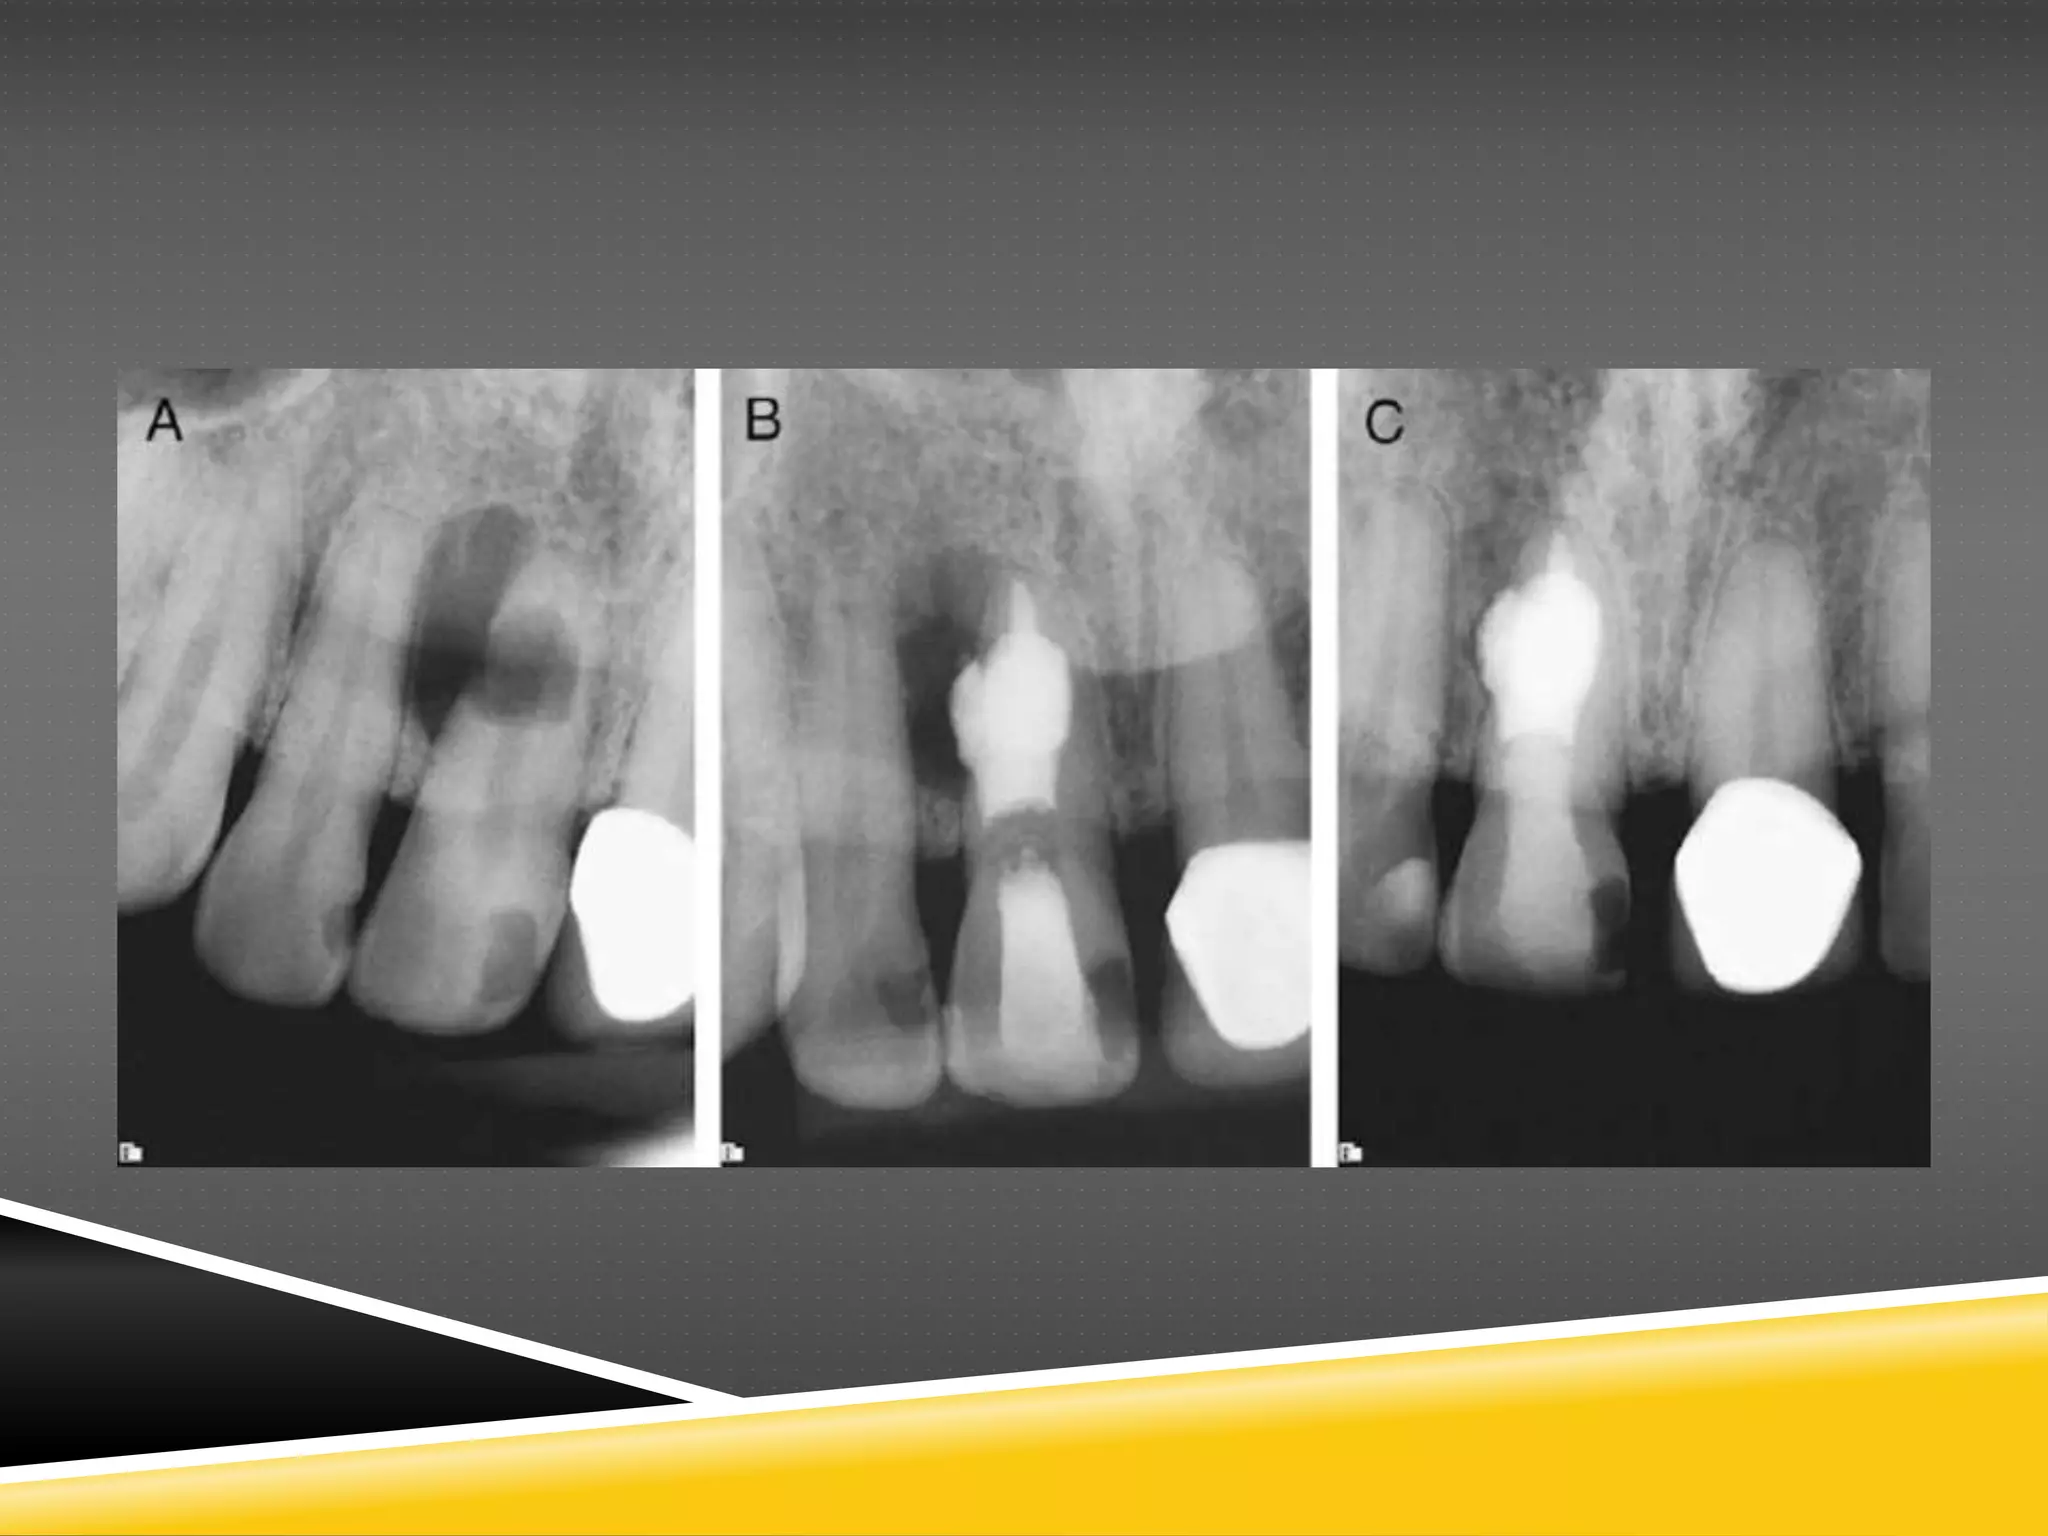

Root-end Filling afterApicoectomy In root canal therapy where an apical infection is persistent, an apicoectomy may be required. Flap is raised over the tooth and the root tip is resected and a cavity created (3–4 mm) in the root tip removed. Retrograde application of MTA to the root tip cavity is completed.

Internal & externalroot resorption & obturation In internal resorption, root canal therapy is performed, a putty mixture of MTA is inserted in the canal using pluggers to the level of the defect. Gutta percha and root canal sealer are placed above the defect to complete the root canal treatment. In direct cases, the canal may be completely obturated with MTA. The MTA will provide structure and strength to the tooth by replacing the resorbed tooth structure. In external resorption, after root canal therapy is performed, the flap is raised over the tooth and the defect removed from the root surface with a round bur. Retrograde application of MTA to the root surface is then completed.

Lateral or furcationperforation Lateral perforation occurs when an instrument has perforated the root during cleaning & shaping of the canal by the dentist. If it happens, one should finish cleaning & shaping of the canal, irrigate the canal with sodium hypochlorite to disinfect it and dry it with a paper point. The perforation can be sealed with a thick mixture of an MTA-type product, preventing bacterial ingress. Make sure that you can locate the canal while the MTA has not set and remove the excess material from the area.

Apexification (Necrotic pulp) Whenthe root is incompletely formed in adolescents and an infection occurs, apexification can be performed to maintain the tooth in position as the roots develop. In case of non-vital pulp: 1. Isolate the tooth with a rubber dam 2. perform root canal treatment. 3. Mix MTA and insert it to the apex of the tooth, creating a 3 mm thickness of plug. 5. Fill the canal with sealer and gutta percha. Alternatively, revascularization techniques are being used where an antibiotic is locally administered. Later a blood clot is formed in the canal and a coronal plug of MTA is placed.

Apexogenesis (Vital pulp) Theprocess of maintaining pulp vitality during pulpal treatment to allow continued development of the entire root (apical closure occurs approximately 3 years after eruption). 1. Isolate the tooth with a rubber dam 2. Perform a pulpotomy procedure. 3. Place the MTA material over the pulp and close the tooth with temporary cement until the apex is completely formed. MTA can be used in a one step or a two step approach. It can be used as a powder or a Wet Mix. However a study found that all these approaches have shown to be equally effective